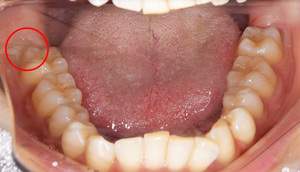

口腔内写真

麻布十番歯科での右下の親知らずが真横に生えている症例の口腔内写真

右下の親知らずが気になると言う主訴でいらっしゃった患者様です。

レントゲンで確認すると、真横にはえており、さらに、下歯槽神経と接触しているようにみえます。

根の形は先細りの形態ですので、抜くのはそこまで難しくないと思われます。根の形の最終確認と、下歯槽神経の位置確認のためにCTを撮影することにしました。